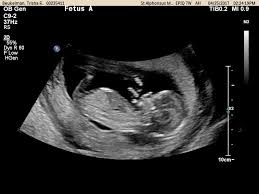

13 Week Twins In The Womb Week By Week, Twin Pregnancy Week By Week Symptoms And Development Pampers, That's because twin moms can have more of the pregnancy hormone hcg in their systems.. 2230 grams / 4lbs, 14oz. Your babies are approximately 7,5 cm (2.95 inches) from head to rump when you're 13 weeks pregnant with twins. If your nausea and vomiting is super severe, definitely bring it up to your ob. 3089 grams / 6lbs, 12oz. When do you start showing with twins?

Your babies are approximately 7,5 cm (2.95 inches) from head to rump when you're 13 weeks pregnant with twins. The average gestational age for twins at birth is 36 weeks. Estimated fetal weight for twins fetal growth chart fetal weight chart full term for twins twin fetal growth chart twin pregnancy week by week twin pregnancy: What would 13 weeks pregnant feel like? Jul 30, 2018 · 2561 grams / 5lbs, 10oz. When did you start showing with twins? When do you start showing with twins? Lowest prices from hundreds of sites all in one place.

Estimated fetal weight for twins fetal growth chart fetal weight chart full term for twins twin fetal growth chart twin pregnancy week by week twin pregnancy: It might soon be time to shop for a larger, more comfortable bra. We compiled some of the best tips, tricks, and facts about being 13 weeks pregnant with twins. Lowest prices from hundreds of sites all in one place. Your complete guide twin weight chart. Twin pregnancy symptoms and conditions. Your babies are approximately 7,5 cm (2.95 inches) from head to rump when you're 13 weeks pregnant with twins. Women who are carrying twins or multiples in their wombs tend to have it a tad more difficult than those who are pregnant with a single baby. Jul 30, 2018 · 2561 grams / 5lbs, 10oz. The first trimester is the first three months or until 13 weeks pregnant with twins. Lowest prices from hundreds of sites all in one place. If you're 13 weeks pregnant with twins, you might still be experiencing some morning sickness and fatigue. 3089 grams / 6lbs, 12oz.